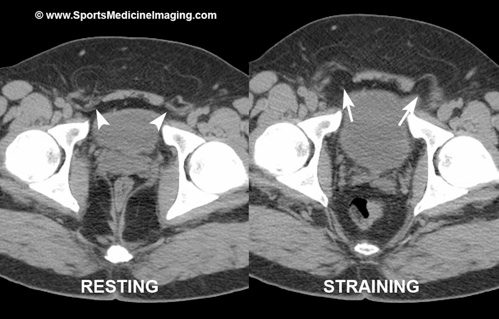

בתמונות ניתן לראות את מבנה הקיר האחורי של המפשעה

ואת הדגמת החולשה של הקיר האחורי בהרניה של ספורטאים ע"י בדיקת הדמיה; תחילה במנוחה (משמאל) ובהמשך התבלטותו קדימה בזמן מאמץ (מימין)